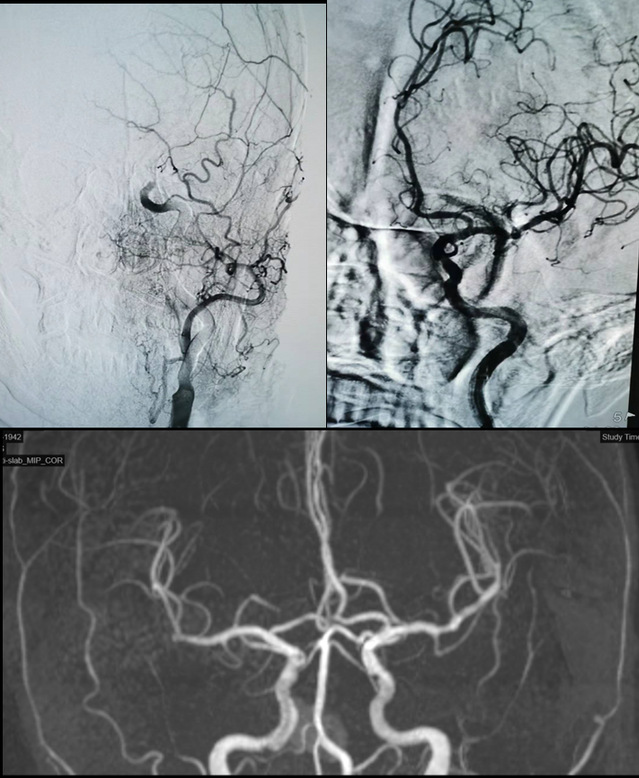

抵达加勒比扑克 后,加勒比扑克 开启卒中绿色通道,并完善急诊头颅CT等检查,最终被诊断为“急性脑栓塞”。最后,在卒中团队的统筹安排下,病人被迅速送至手术室,进行了脑动脉取栓手术。术中造影发现患者一侧大脑中动脉闭塞,手术团队运用支架联合抽吸导管技术,成功取出血栓,术后沈大爷的肢体偏瘫情况好转。